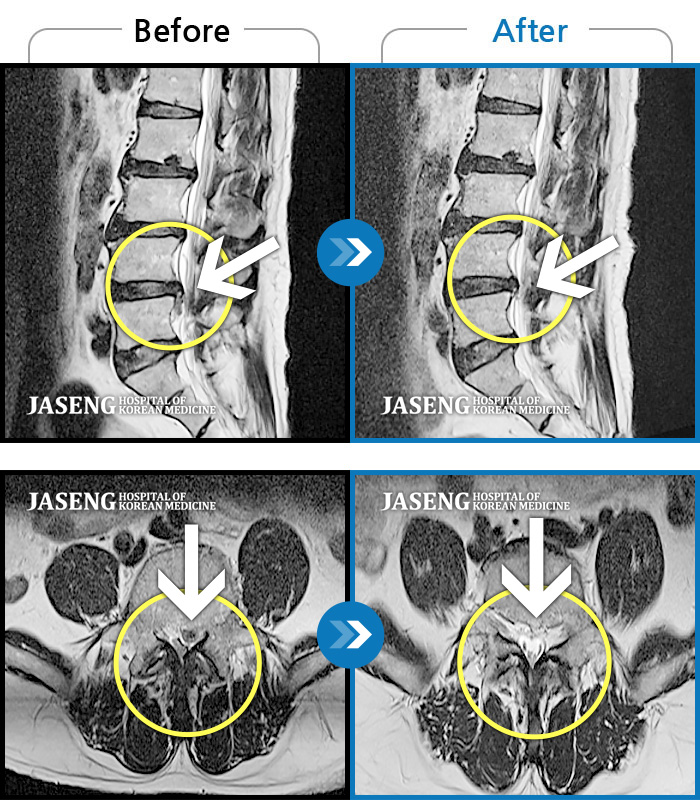

Before

After

환자에게 사전 동의를 받아 동일 조건에서 촬영되었습니다.

개인에 따라 치료 후 부작용이 발생할 수 있으니 의료진과 상담 후 치료를 진행하시기 바랍니다.

갑작스러운 허리 및 왼쪽 하지 통증으로 내원

좌측 허리, 골반, 다리 바깥쪽으로 통증과 저림